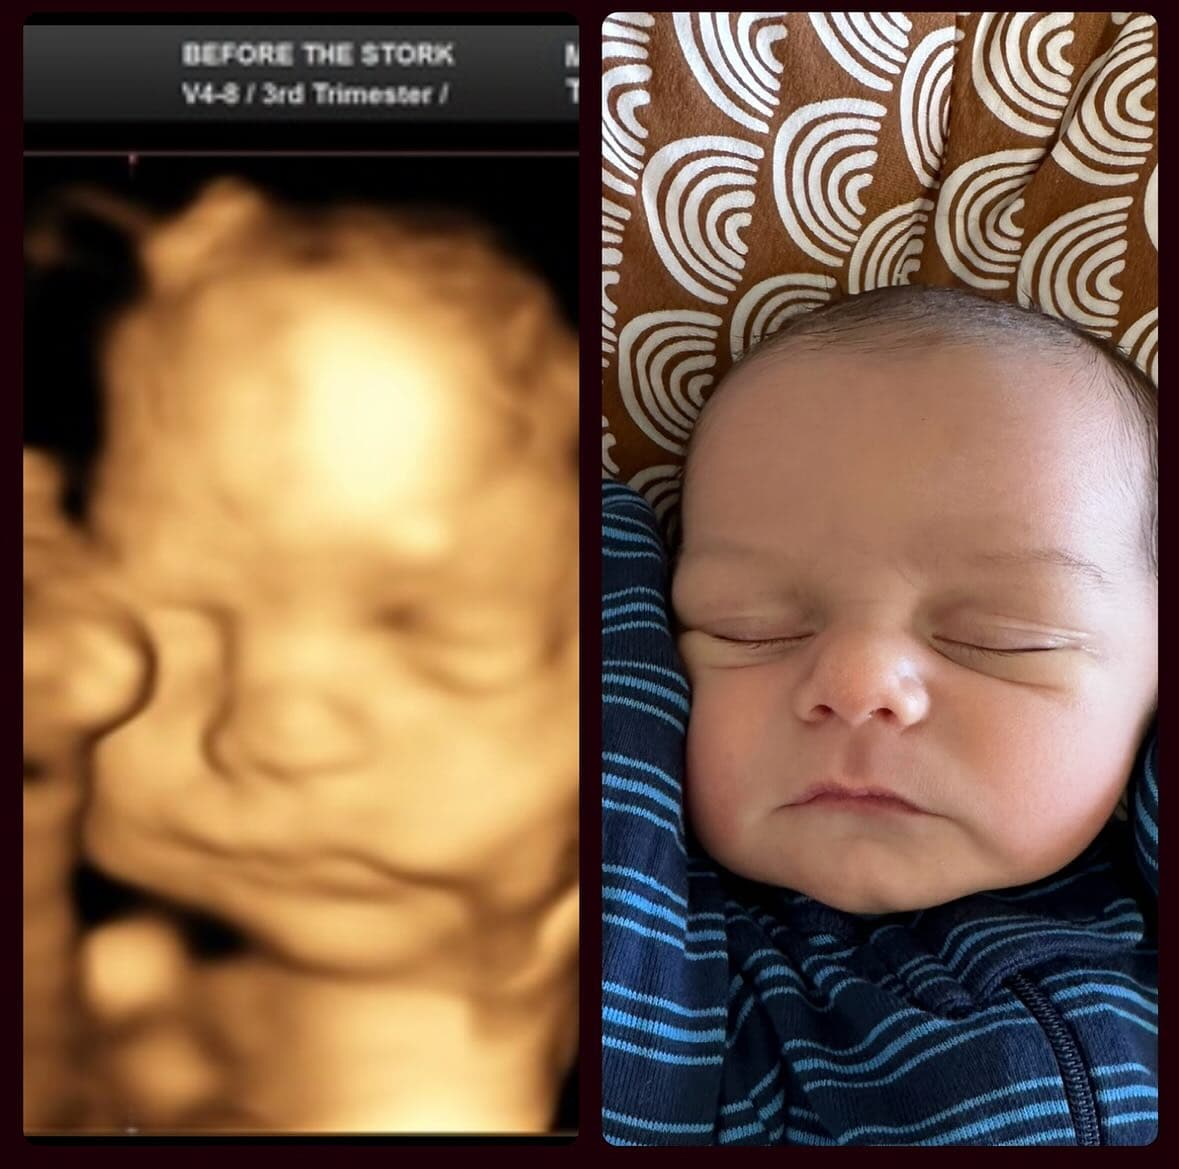

The most common reaction after birth? "The nose looks nothing like the ultrasound." Pregnancy forums are full of parents sharing their 3D ultrasound next to their newborn photo, and the difference is striking. Wide, flat ultrasound noses turn into perfectly normal (often tiny) baby noses.

Ultrasound studios publish before-and-after galleries showing 3D scans alongside the born baby—and you can see the pattern clearly: the nose is almost always wider on the scan. Browse real examples at Fetal Vision Imaging, 3D Baby Boutique, and Baby Moments Ultrasound. Not every case is dramatic—some noses match closely—but the wide-nose effect is by far the most common outcome.